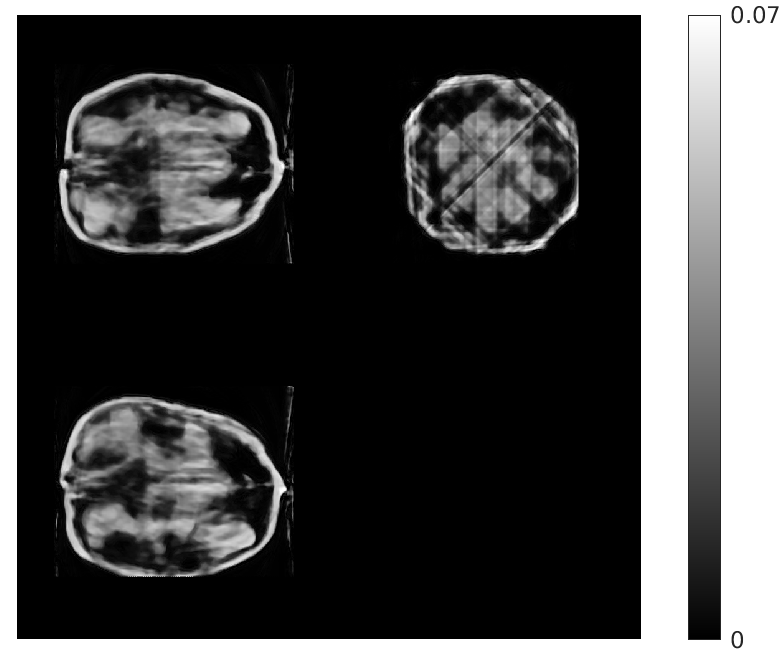

Fig. 5 shows walnut 1 from our test dataset being progressively reconstructed from 8 projections across the stages of our algorithm; as the stages progress, more features are restored in the reconstructed walnut, until the improvements become incremental. The residual streaking artifacts outside the walnut are mitigated in the reconstructions from the third and fourth stages.

| Stage 1 | Stage 2 |

![]() |

| (a) (MAE: 0.32) | (b) (MAE: 0.29) |

| Stage 3 | Stage 4 |

| (c) (MAE: 0.27) | (d) (MAE: 0.26) |